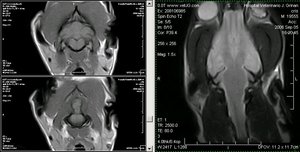

Detalle del mielencéfalo canino en una MRI. Cortes transversales pot. en T1 y corte dorsal pot en T2